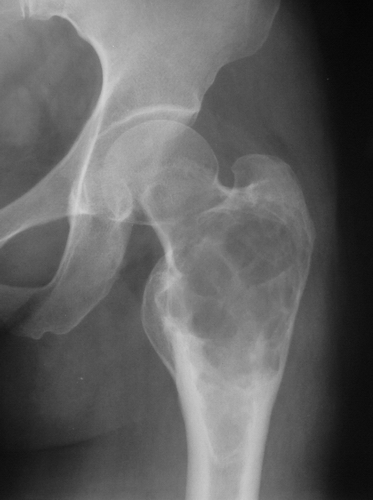

患者,女,53岁。右髋部疼痛数月。

股骨上段膨大,其内见囊性病灶及骨嵴,下部骨质密度增高,首先考虑骨纤,与动脉瘤样骨囊肿鉴别

股骨上段膨大明显,其内见囊性病灶及骨性间隔,下部骨质密度增高,皮质变薄,无明显硬化边。考虑1骨巨细胞瘤。2骨纤